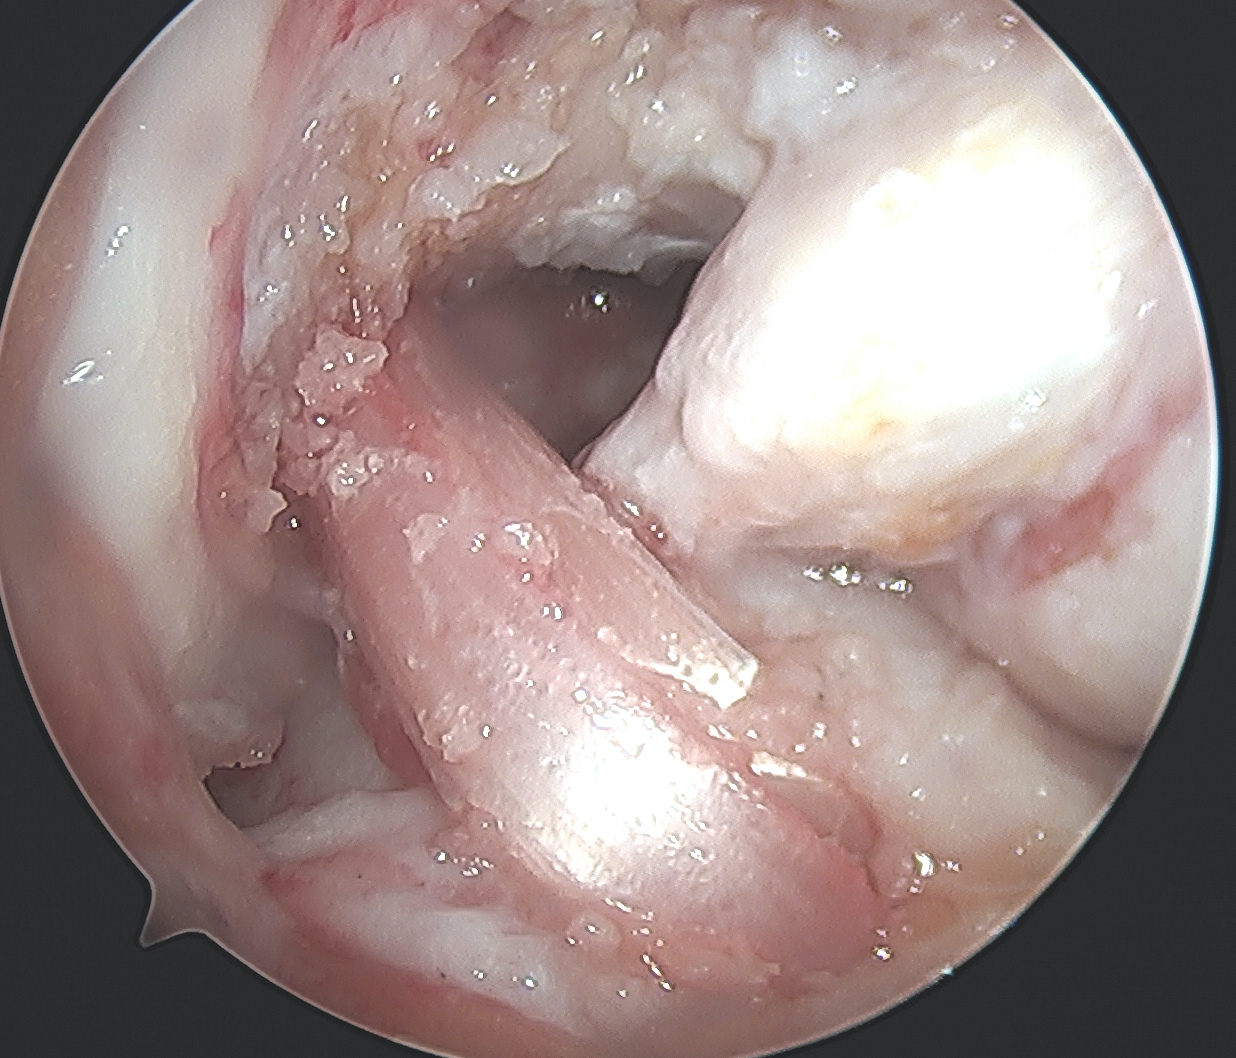

MCL Reconstruction

Femoral side

- use previous proximal medial incision

- identify PCL femoral tunnel

MCL insertion

- identify adductor tubercle (insertion point of adductor magnus tendon)

- medial epicondyle is 12 mm distal and 8 mm anterior to adductor magnus

- insertion point of MCL is 4 mm proximal and 4 mm posterior to medial epicondyle

- can use xray (intersection of the posterior femoral cortex and blumenstaat's line)

Drill MCL femoral tunnel

- 9 x 25 mm

- aim 40o anterior and 40o proximal to avoid PCL tunnel convergence

- insert bony plug and fix with a 7 x 20 mm metal screw

MCL tibial fixation

- use instruments to make passage for tendon end of achilles allograft

- fixation point is 6 - 7 mm below tibial joint line

- use a 4.5 mm cortical screw from large fragment set

- use a spiked soft tissue washer from the large fragment set

- can place soft tissue anchors on proximal tibia for two point fixation